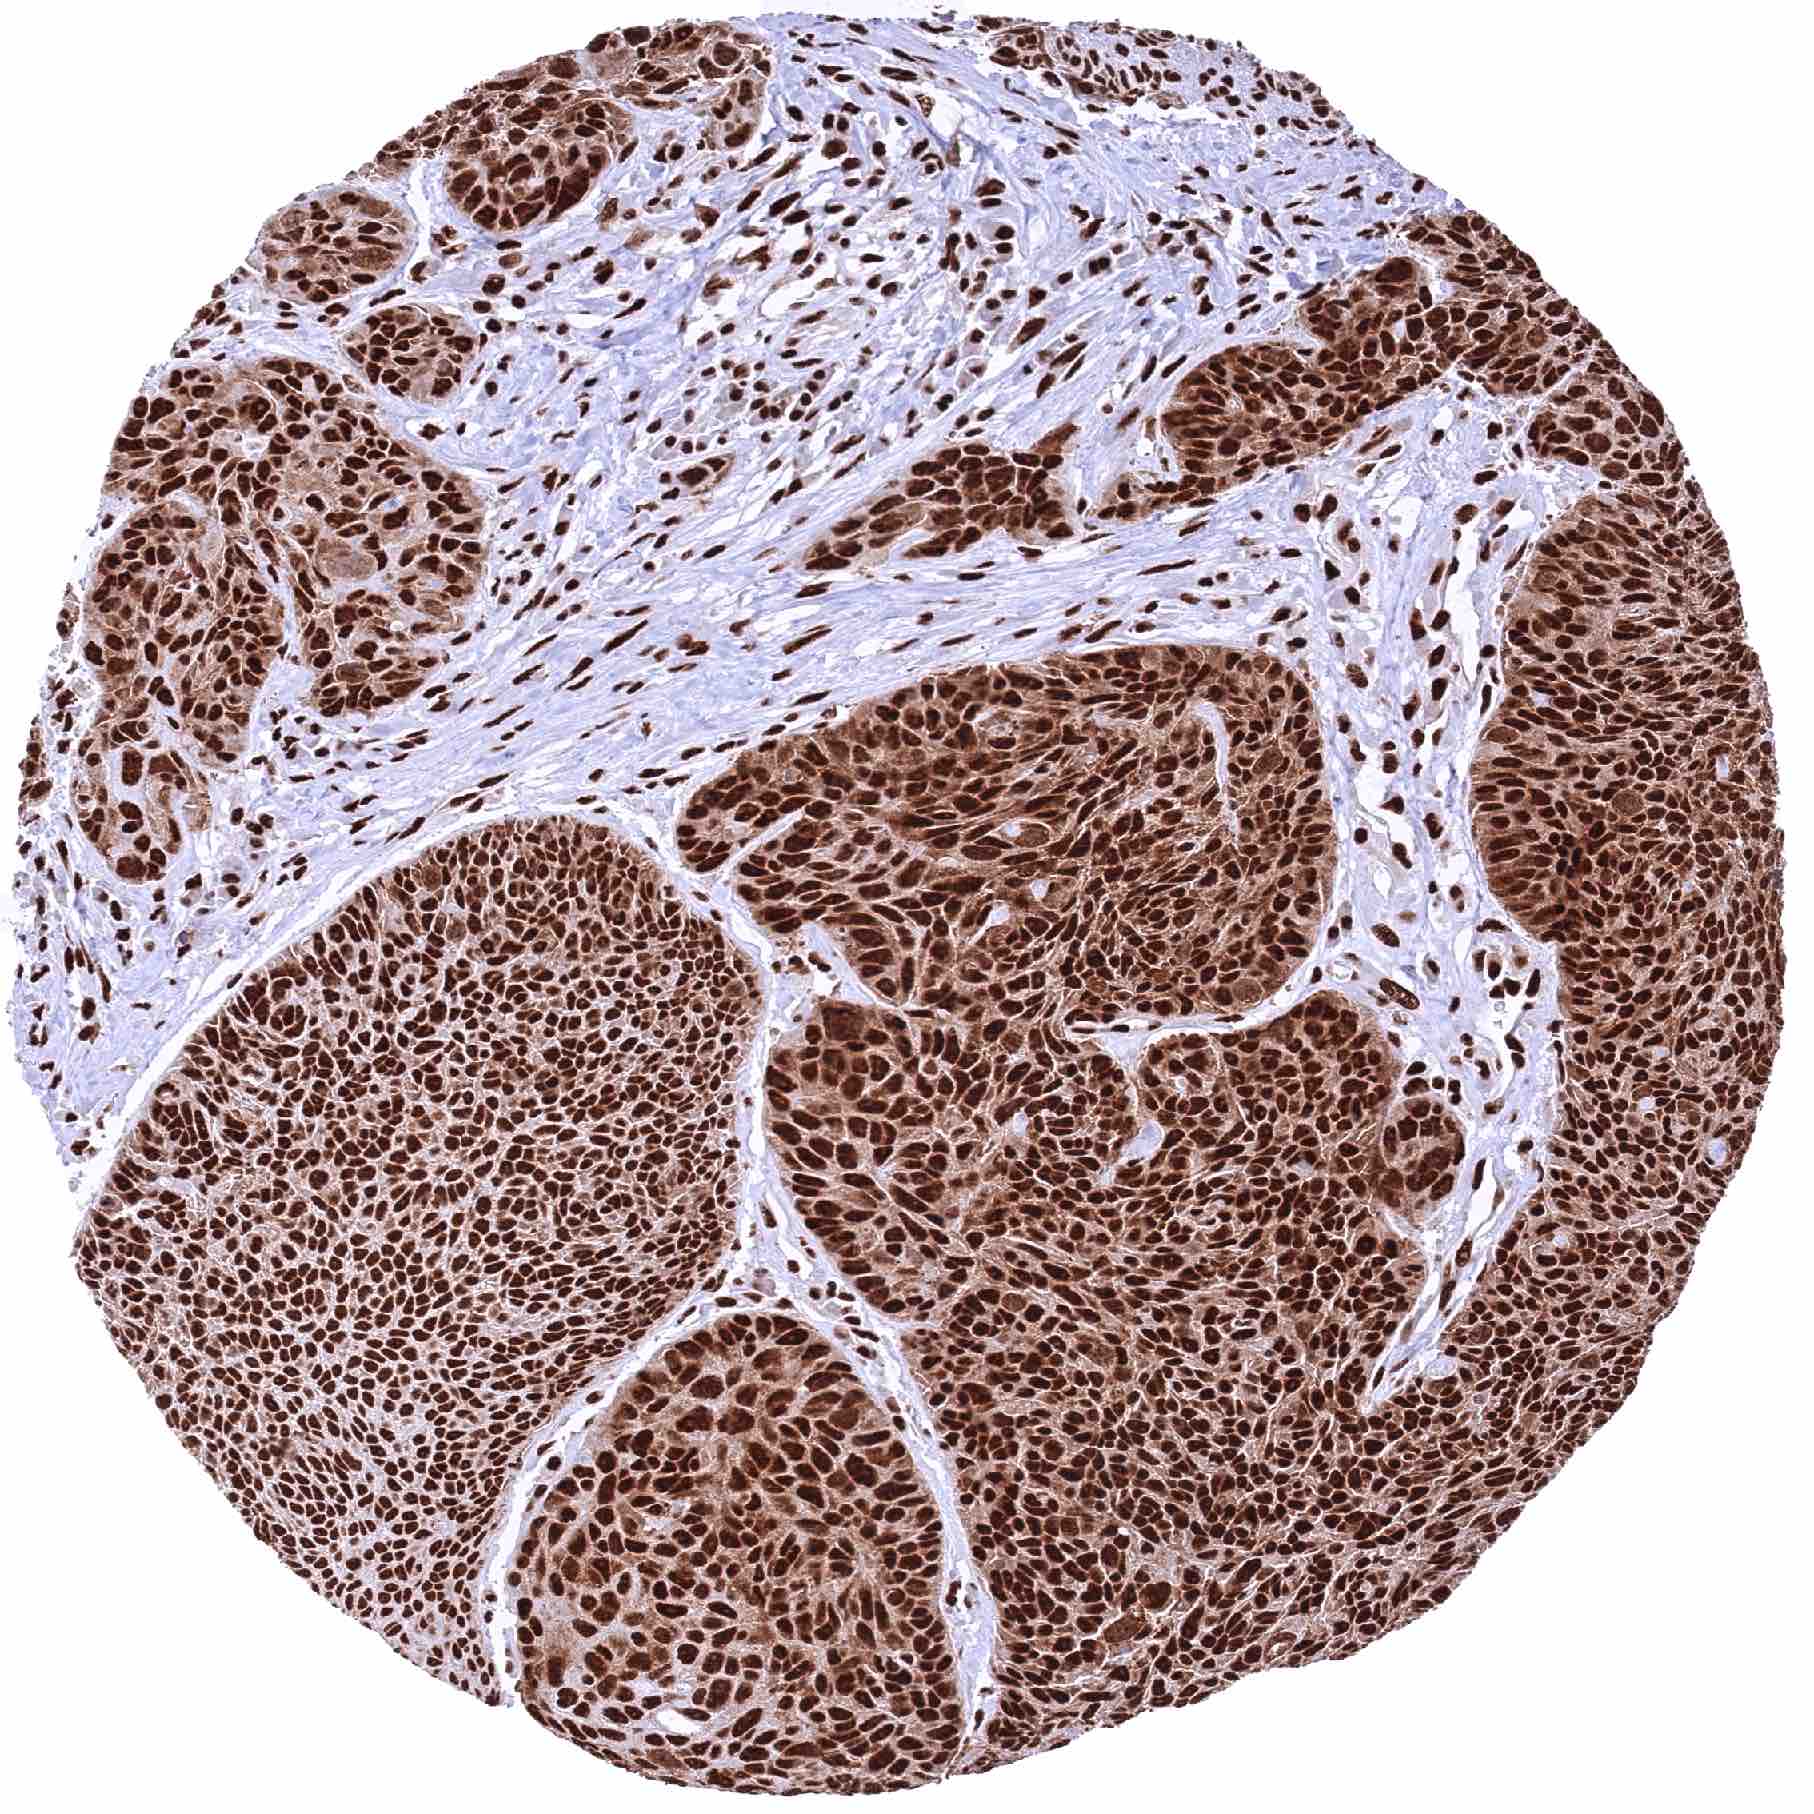

Lymph node – Diffuse large B-cell lymphoma showing a strong nuclear MRE11 positivity of tumor cells